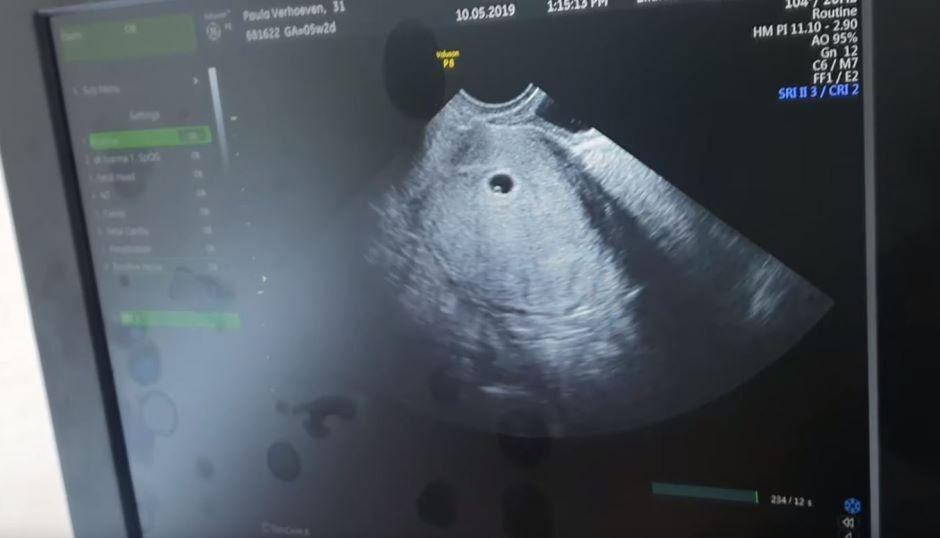

PELAKON Baim wong akhirnya mengumumkan isterinya baru sahaja disahkan hamil selepas setahun mendirikan rumah tangga.

Baim dan isterinya, Paula Verhoeven yang juga aktress popular Indonesia membuat pengumuman tersebut melalui saluran Youtube mereka beberapa hari lalu.

Baim umum Paula sedang hamil beberapa hari lalu.